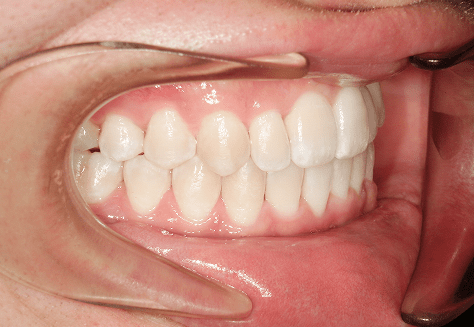

M.H

治療前

治療後

主訴

前歯が出ている。下の歯並びが特に気になる。奥歯でしっかり噛めない。

診断

上顎前突・叢生・シザーズバイト

年齢/性別

20代/男性

抜歯部位

下顎両側大三大臼歯(口腔外科にて)

上顎両側第一小臼歯・下顎左側側切歯

(当院にて5,500円×3) -

使用装置

上下エッジワイズ→インビザライン(PBM使用)

保定装置

上下ビベラリテーナー

診察料金

5,500円×44回

治療期間

3年6カ月